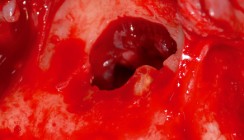

Im OPG (Abb. 1) sieht man einen osteolytischen Prozess im Bereich der Zahnwurzel des Zahnes 21, die als relativ große apikale Parodontitis bezeichnet wurde. Die Aufhellung hat einen Durchmesser von circa 1cm, und im Röntgenbild scheint es so, als ob die Wurzel des Zahnes 22 ebenfalls betroffen ist. Zum besseren Verständ-nis der sonografischen Untersuchung wurde auf einem Schädelmodell die Ultraschallsonde entsprechend dem Patientensitus appliziert. Zur einfa-cheren Orientierung wurde im Modell der Zahn 22 entfernt, sodass die Al-veole gut sichtbar ist (Abb. 2). Die sonografische Aufnahme zeigt einen relativ gut begrenzten Bereich, der in der Peripherie von einem homogenen reflexreicheren Gewebe gebildet wird. Zentral zeigt sich eine echoarme Struktur. Nach dorsal ist eine deutliche Schallverstärkung sichtbar. Es handelt sich um ein typisches sonografisches Bild einer Kieferzyste mit Flüssigkeitsansammlung (Abb. 3). In der Abbildung 4 sieht man den gleichen Situs, mit einer etwas andere Angulation der Ultraschallsonde. Dadurch erscheint zentral in der Kieferzyste eine weißliche, reflexreiche Struktur. Hierbei handelt es sich um Anteile der Zahnwurzel des Zahnes 21. Nach Auswertung der Bilder wurde eine Zystektomie mit gleichzeitiger Wurzelspitzenresektion und Wurzelfüllung vorgenommen. Im Operationssitus zeigte sich eine Ausdehnung der Zyste nach kranial und palatinal. Da der Zahn 21 ausreichend stabil im Knochen stand, konnte auf eine zusätzliche Schienung des Zahnes verzichtet werden.